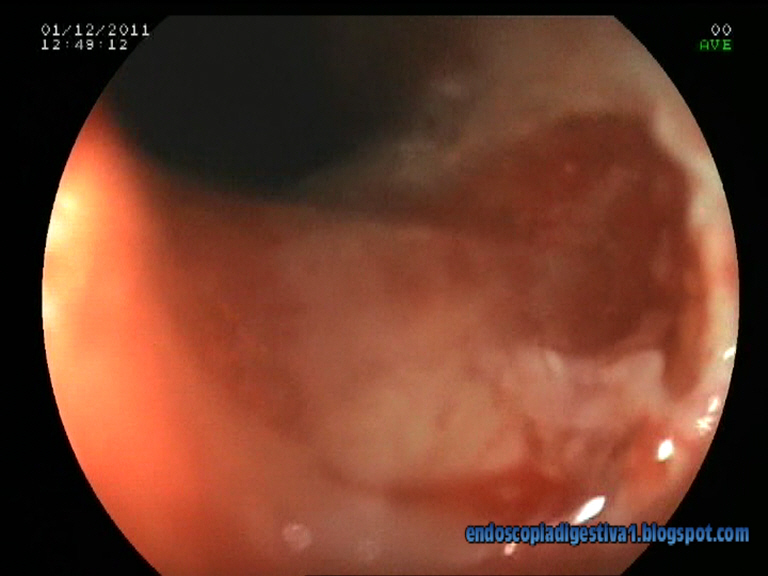

Paciente varón de 78 años de edad con antecedentes de HTA, hiperlipemia, esófago de Barrett corto de > 7 años de evolución (controles endoscópicos anuales con metaplasia intestinal, aunque displasia leve en una de las muestras de la gastroscopia realizada a finales de 2010) y cáncer de colon sincrónico (recto, colon descendente y colon ascendente) intervenido en octubre del presente año (colectomia subtotal; estadiaje T3-N0-M0) . En la gastroscopia de control del esófago de Barrett realizada en agosto, se advierte una nodulación de 3 mm con ligera depresión central justo por encima de la unión GE que histológicamente se define como una displasia severa-carcinoma in situ. Se decide realizar mucosectomía de la lesión con bandas elásticas y resección por debajo de ésta que cursa sin complicaciones inmediatas. El estudio histológico de la pieza confirma la histología descrita, no apreciandose datos de adenocarcinoma microinvasor (T2). La idea final es aplicar una técnica de ablación con radiofrecuencia tipo HALO 360º para completar el tratamiento de la mucosa con epitelio de Barrett.

El esófago de Barrett con displasia severa o carcinoma intramucoso es suceptible de un tratamiento endoscópico con intención curativa. Sin duda, la mejor técnica es la disección endoscópica submucosa (ESD), pero es compleja, con una tasa de complicaciones no desdeñable y está muy poco extendida en Occidente. La mucosectomìa endoscópica es una alternativa bastante mas sencilla, con % de complicaciones menor, que si ha tenido aceptación en los paises occidentales. Los dos métodos mas difundidas son el sistema de bandas Duette (Cook) y el de Caps sin ligadura (Olympus). El primero es algo mas sencillo ya que es muy similar a la ligadura de varices con bandas. Se exponen dos ejemplos de las técnicas descritas del DAVE Project:

En nuestro centro estamos en espera de disponer de alguno de estos 2 métodos. Mientras tanto hemos optado por una alternativa mas barata usando el sistema de bandas elásticas (Speedband 7) de Boston Scientific en base al ejemplo que Max Yoza expone en su blog de endoscopia digestiva ENDOTUBE (http://www.endotube.blogspot.com/2010/10/mucosectomia-en-esofago-de-barrett-con.html). Está claro que es mas engorroso porque obliga a introducir un endoscopio cada vez que se va a resecar una banda, pero te saca del apuro.